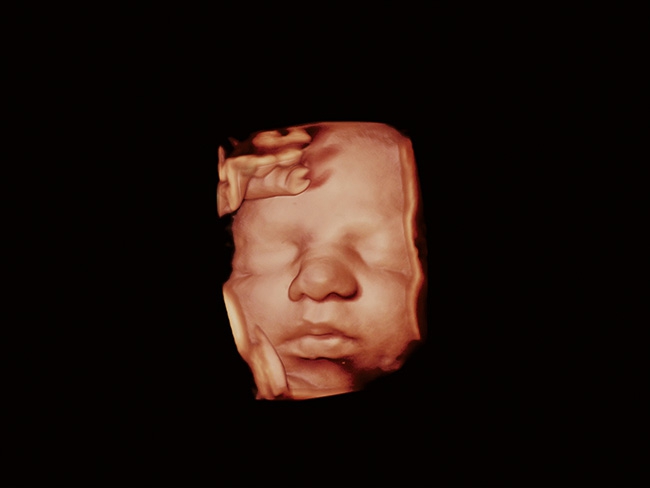

Aplio a550 может работать с линейным матричным датчиком и поддерживает новейшие монокристаллические датчики. Также Aplio a550 поддерживает большое количество дополнительных опций, таких как - SMI, Компрессионная эластография, Эластография сдвижной волны, Smart Fusion, исследования с использованием контраста (CEUS), 3D реконструкции в реальном времени (4D), функции автоматической оценки подвижности миокарда и фракции выброса.

4D:

Да